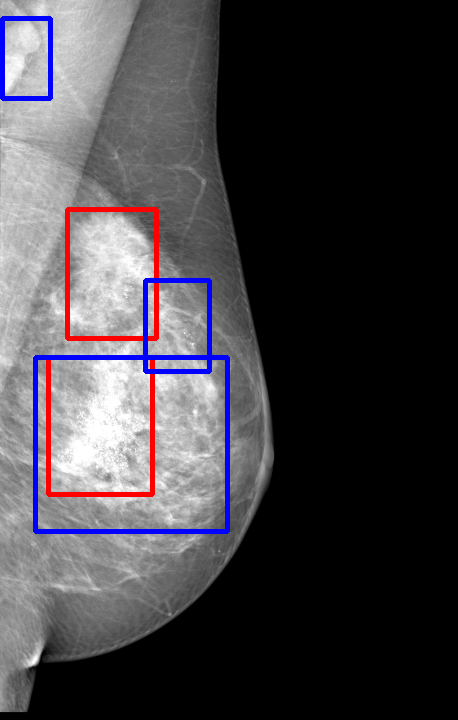

UDA has been extensively studied in case of natural images, utilizing techniques such as adversarial learning [21],pseudo-label training [6, 21, 40], image-to-image translation [40], graph reasoning [20], and adaptive mean Teacher training [6], improving domain adaptation efficiency of object detectors. Recently multiple works focused on using Mask autoencoders (MAE) methods in large-scale pretraining for vision models, involving masking parts of input and reconstructing them [12, 33]. However, these approaches overlook domain shifts. Alternatively, widespread utilization of Teacher-Student models, wherein a Teacher provides pseudo-labels for target domain (unlabeled images) to supervise a Student model, leads to notable adaptation improvements [40, 43]. However, these techniques face the challenge of incorrect predictions and excessive false positives per image due to low-quality pseudo-labels, particularly for medical imaging problems. Pseudo-labels are filtered from the Teacher model’s outputs based on the confidence score threshold. Selecting numerous pseudo-labels with low thresholds leads to inclusion of incorrect predictions, and compromising performance. Conversely, higher thresholds yield a limited number of pseudo-boxes, resulting in sub-optimal supervision. Existing Teacher-Student models often produce pseudo-labels riddled with errors and false positives, as illustrated in Fig. 1(a) and Fig. 1(b). Though [21, 40, 43] utilize techniques like adversarial alignment, weak-strong augmentation, and selective retraining of Student model to minimize the false positives in pseudo-labels, these approaches fail on medical images.

Contributions of this work. We note that screening mammography inherently differs from natural images, with breast abnormalities such as masses, asymmetries, and micro-calcifications, typically much smaller in comparison to the salient objects present in natural images, emphasizing the need for approaches specific to this problem. To address these issues, we make following contributions in this work: (1) We introduce D-MASTER, a transformer-based Domain-invariant Mask Annealed Student Teacher Autoencoder Framework for cross-domain breast cancer detection from mammograms (BCDM), integrating a novel mask-annealing technique and adaptive confidence refinement module. Unlike pretraining with mask autoencoders (MAEs) [12], leveraging massive datasets for training and then fine-tuning on smaller datasets, we present a novel learnable masking technique for the MAE branch that generates masks of different complexities, which are reconstructed by the DefDETR [44] encoder and decoder. Our approach, as a self-supervised task on target images, enables the encoder to acquire domain-invariant features and learn better target representations as shown in Fig. 1(c). (2) In Teacher-Student model, since the pseudo-label noise generated by the Teacher affects the Student model severely, we propose an adaptive confidence refinement module that progressively restricts the confidence metric for pseudo-label filtering. During the initial adaptation phase, soft confidence is applied allowing more pseudo-labels to learn better target representations. Subsequently, as confidence gradually increases, the focus shifts towards enhancing detection accuracy by prioritizing more reliable pseudo-labels. (3) We release a bounding box annotated subset of 1000 mammograms from the RSNA Breast Screening Dataset (referred to as RSNA-BSD1K) to support further research in BCDM. (4) We setup a new state-of-the-art (SOTA) in detection accuracy for UDA settings. We report a sensitivity of 0.74 on INBreast [25] and 0.51 on DDSM [18] at 0.3 FPI, compared to 0.61 and 0.44 using current SOTA respectively. Significant performance gains are also observed on our in-house and RSNA-BSD1K datasets.